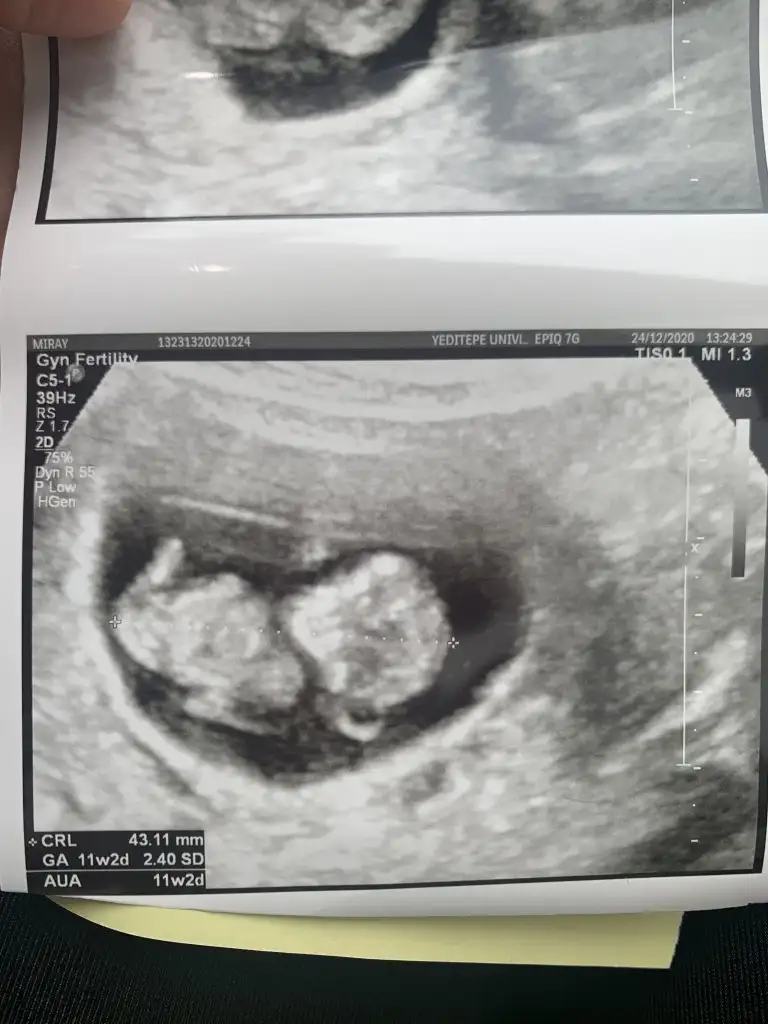

Erkek gibi sanki emin olamadım 12-13 hafta olursa paylasinIkra meyra merhaba ikisi de Vajinal ultrason 7 haftalık ve 11 haftalık. Rica etsem tahmin yapabilir misiniz?

Teşekkür ederim canım çok şükürSevgiliIkra meyra öncelikle nasılsınız? Size daha önce sormuştum ama orada daha minikti siz tekrar gönderin demiştiniz burada 13 haftalık. Belli oluyor mu?

Kız görünüyor tabi en iyi 11 12 13 haftalar olmalıİkra meyra bunada bakabilirmisin bende tahminin tuttu bu da ablamın vajinal çekilmiş 6 haftalık

Evet ben anketi oyladım 2 gün önce çook teşekkür ederimKız görünüyor tabi en iyi 11 12 13 haftalar olmalıprensesin sağlıkla gelsin canım anketimi oyladinizmi